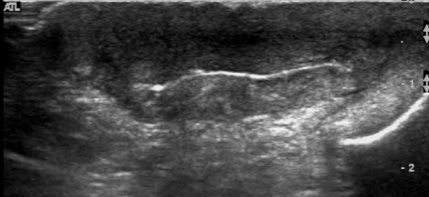

Figure 1 for case Hidradenitis suppurativa

Figure 1